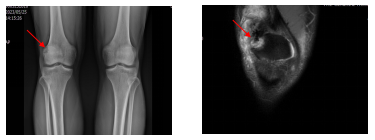

也被称为分裂髌骨,是一种常见的生理现象。在X线或CT等影像学检查中,可以观察到正常人的髌骨只有一列,而二分髌骨则有两列。这种特征性的表现通常不会引起任何症状,常常在受到外部压力或损伤时,可能会引发疼痛或不适。

对于二分髌骨的诊断,主要依赖于影像学检查,如X光、CT或MRI等。医生会根据这些检查结果,评估二分髌骨的状态,包括是否有疼痛、炎症或其他并发症。同时,医生还会进行全面的体格检查,以了解患者的疼痛程度、活动能力以及是否有其他潜在的疾病。

图片来源于文献:潘子翔,邢学武. 二分髌骨的诊断和治疗. 中华外科杂志,2016,54(4):305-308.